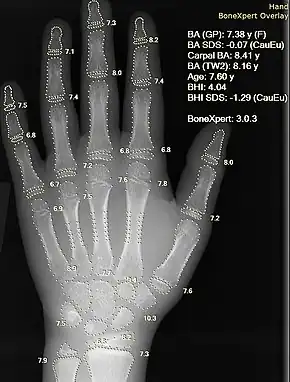

X-ray of a hand with calculation of bone age analysis

Some radiologists, like teleradiologists, have no interaction with patients. Other radiologists, like interventional radiologists, primarily interact with patients and spend less time analyzing images. Diagnostic radiologists tend to spend the majority of their time analyzing images and a minority of their time interacting with patients. Compared to the healthcare provider who sends the patient to have images interpreted by a diagnostic radiologist, the radiologist usually does not know as much about the patient's clinical status or have as much influence on what action should be taken based on the images. Thus, the diagnostic radiologist reports image findings directly to that healthcare provider and often provides recommendations, who then takes the appropriate next steps for recommendations about medical management. Because radiologists undergo training regarding risks associated with different types of imaging tests and image-guided procedures,[16] radiologists are the healthcare providers who generally educate patients about those risks to enable informed consent, not the healthcare provider requesting the test or procedure.[17]